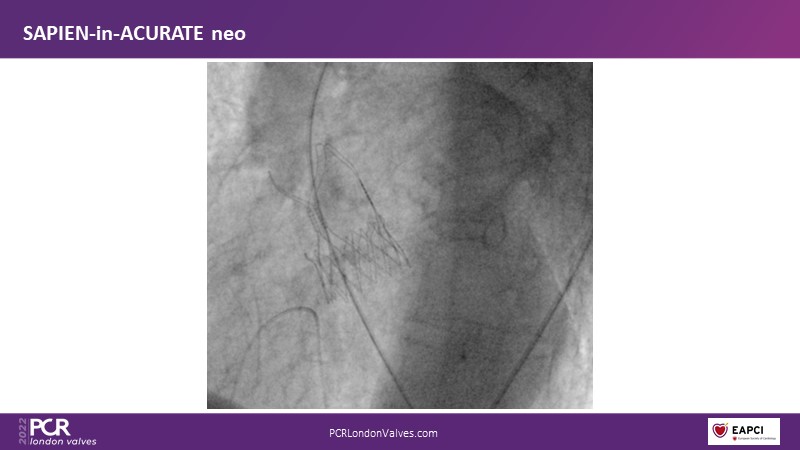

TAVI-in-TAVI - A road map for successful lifetime management

Join a team of experts that guide you through the basics of TAVI-in-TAVI, the procedural planning and techniques of implantation, followed by case examples with different index prostheses.